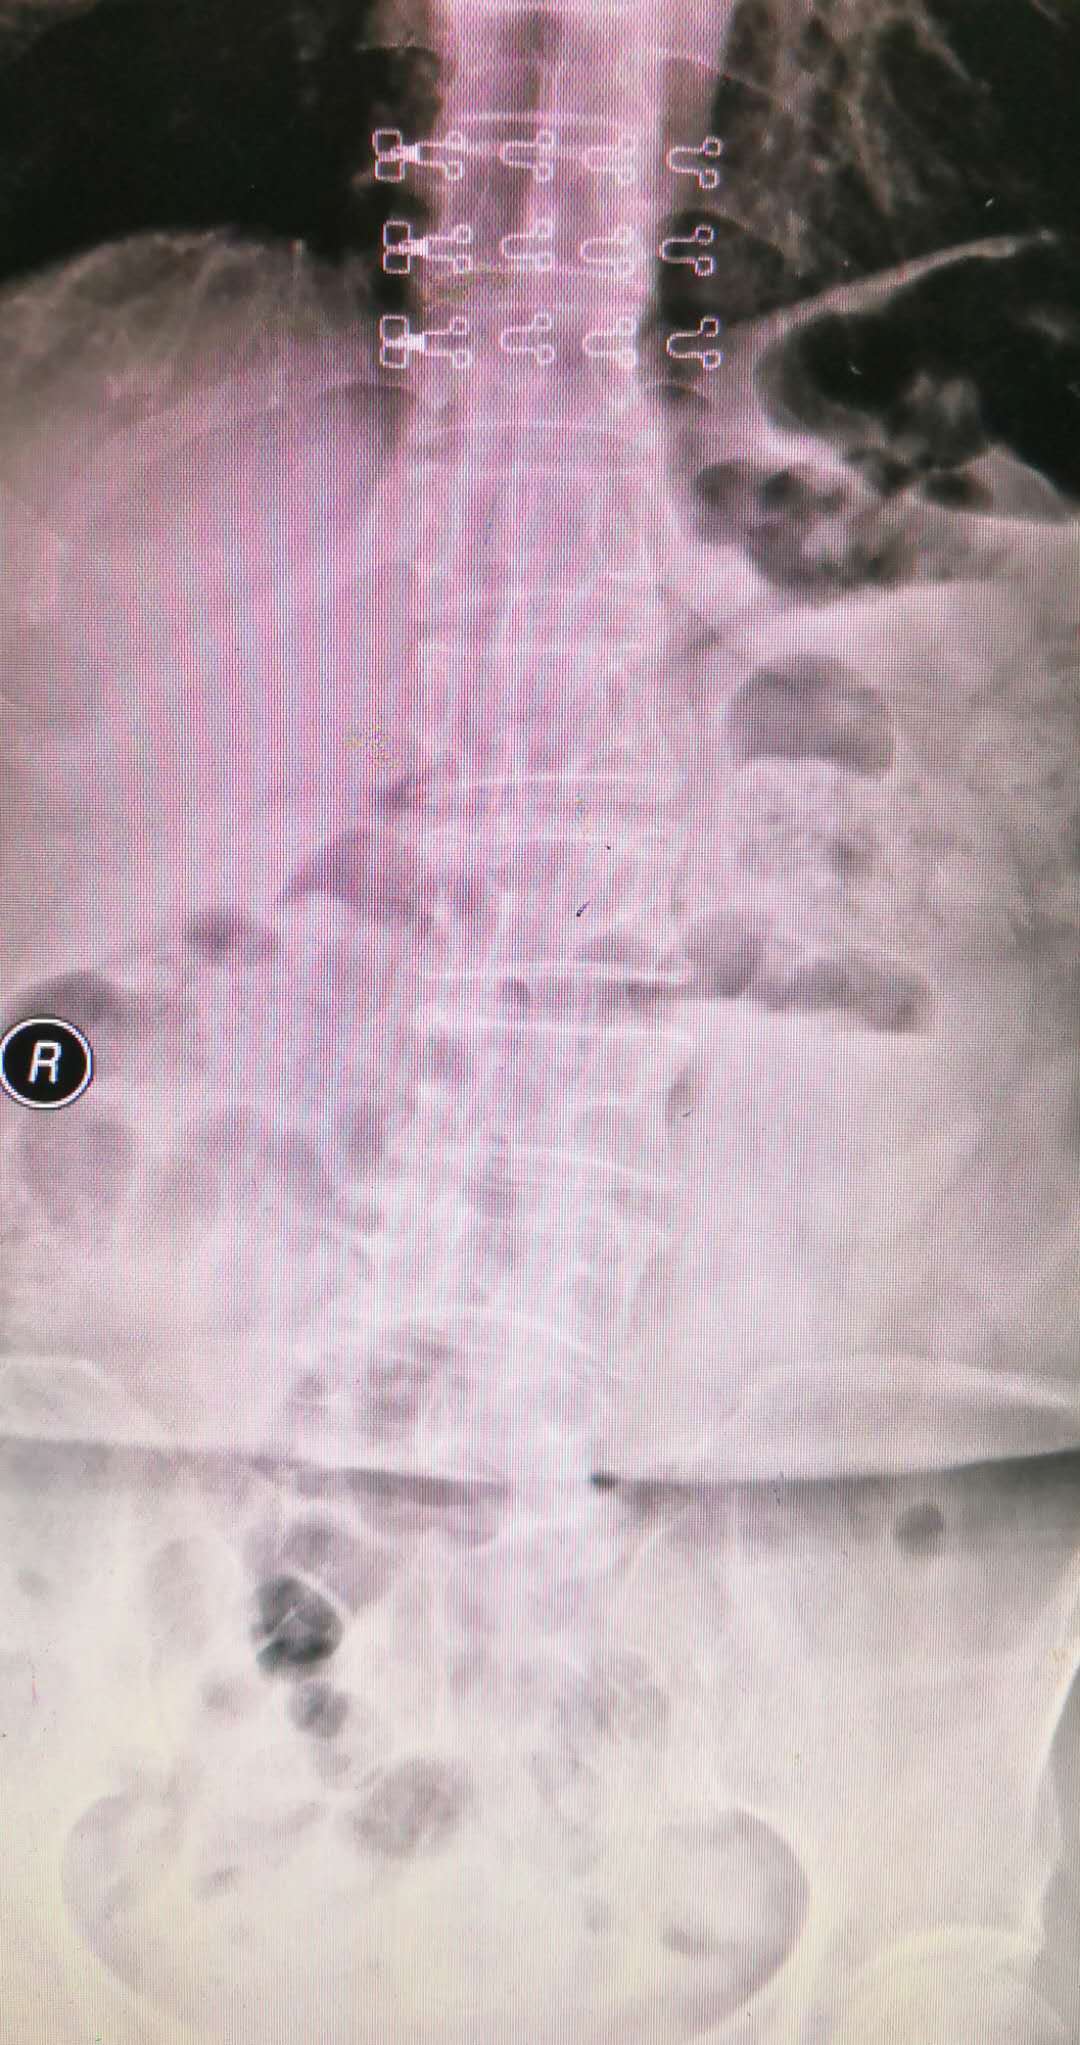

而腰椎不稳的图片完全不一样,如下图所示:

脊柱侧弯,L4椎体前度滑脱